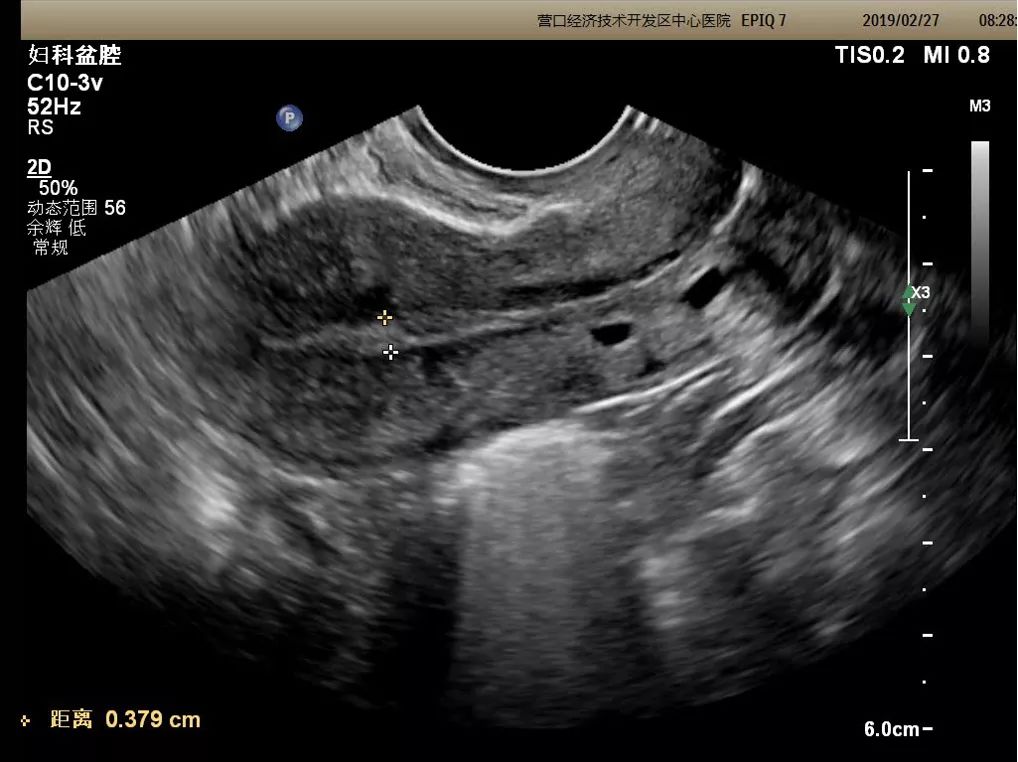

经阴道三维超声

可通过三维重建技术,整体、直观的获得子宫的冠状切面,更加直观的显示子宫外形轮廓、宫腔形态及子宫内膜的连续性,能够弥补二维超声的不足,起到补充及确定诊断的作用,适用于子宫先天性发育异常、宫腔内病变及宫内节育器形态及位置异常等疾病的诊断。

二维成像